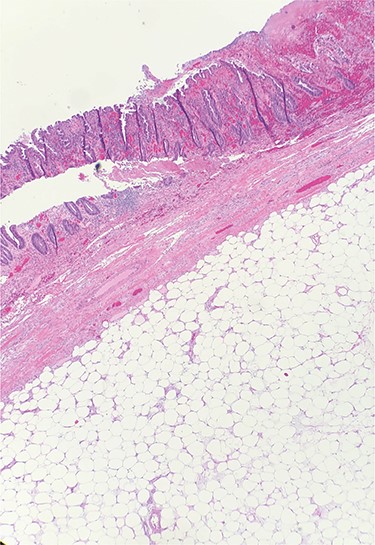

A 54-year-old man presented to his gastroenterologist with a 4-week history of worsening crampy abdominal pain associated with abdominal distention and obstipation. He was admitted urgently to the hospital after CT imaging revealed an evolving large bowel obstruction from transverse colonic intussusception likely secondary to a colonic mass lead point (Fig. 1). The patient underwent colonoscopy, but dusky nonviable mucosa was seen at the leading edge of the intussusceptum (Fig. 2), so no attempt was made to traverse it and the patient was taken for emergent surgical treatment. Using a hand-assisted laparoscopic approach, the cause of obstruction was confirmed to be a long segment of intussuscepted proximal transverse colon traversing the entire splenic flexure into descending colon, with a boggy mass acting as the lead point. The transverse colonic intussusceptum was carefully milked backward from within the descending colonic intussuscipiens to its natural anatomic position. Despite return of pink, viable colon appearance after a decompressive colotomy, some serosal abnormalities and congestion of the right colon from severe distention warranted its resection. An extended right hemicolectomy was performed with a distal transection margin 10 cm distal to the colonic mass origin, followed by stapled side-to-side, functional end-to-end ileocolonic anastomosis. The resected specimen was opened intraoperatively, revealing a large, pedunculated, polypoid mass with soft center consistent with colonic lipoma (Fig. 3). The patient recovered well, with return of bowel function on postoperative Day 3 prior to discharge home. Histopathology confirmed a 9.5 × 5.5 × 4.5 cm submucosal lipoma (Fig. 4) and 12 benign lymph nodes.

Hematoxylin and eosin (H&E) staining of colonic specimen revealing a submucosal lipoma.